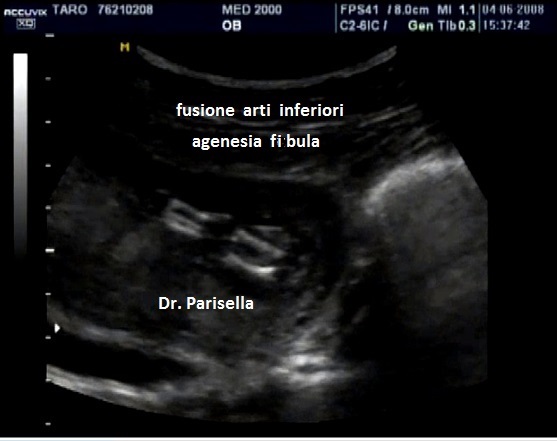

Sindrome o Complesso Femore-Fibula-Ulna OMIM 228200

E' una rara sindrome malformativa caratterizzata da difetti, ipoplasia o aplasia, di femore, fibula e ulna ai quali possono associarsi difetti delle dita.  I difetti delle dita, se presenti, interessano il lato ulnare e/o quello fibulare. Viene classificata in quattro gruppi in base all'interessamento di uno, due, tre o quattro arti.

L'interessamento di femore, fibula ed ulna è caratteristico ma possono essere interessate anche le altre ossa lunghe: la mano (aplasia), la tibia (ipoplasia) e l'omero (ipoplasia).

La coesistenza dell'interessamento di questi tre segmenti ossei da soli è sufficiente a porre la diagnosi di Sindrome o Complesso Femore-Fibula-Ulna, indipendentemente dall'interessamento o meno di altri segmenti ossei. La triade femore-fibula-ulna è patognomonica della patologia.